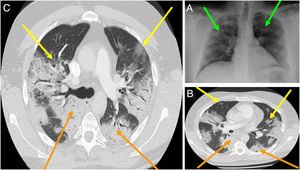

En general, el hallazgo imagenológico principal tanto en las Rx-Tx y las TC-Tx es el de una neumonía atípica u organizada (fig. 3A). En las Rx-Tx se suelen observar opacidades asimétricas irregulares como en vidrio esmerilado, datos de consolidación, con distribuciones bilaterales, periféricas y de los campos pulmonares inferiores. La afección pulmonar tiende a progresar en el trascurso de la infección, por lo que estos hallazgos pueden variar según el momento de evolución en que el cuadro clínico se encuentre; con todo, según la literatura médica, hasta un 20% de los casos no presentan ni presentarán estos hallazgos radiológicos en ningún momento de la enfermedad (fig. 3B)1,53.

A) Radiografía de tórax de un paciente con COVID-19. Las flechas verdes marcan opacidades asimétricas irregulares en ambos campos pulmonares. B)Tomografía de tórax de un paciente con COVID-19, etapa inicial. Las flechas amarillas marcan consolidaciones, las flechas naranjas marcan consolidaciones en vidrio esmerilado. C)Tomografía de tórax de un paciente con COVID-19, etapa tardía. Las flechas amarillas marcan consolidaciones, las flechas naranjas marcan consolidaciones en vidrio esmerilado con patrón reticular e importante distorsión anatómica.

Fuente: Imágenes obtenidas mediante consentimiento de paciente salvaguardando su identidad.

En cuanto a lo referente a las TC-Tx, los hallazgos predominantes son las opacidades en vidrio esmerilado y las consolidaciones distribuidas irregularmente, como si fueran parches, principalmente en la zona medial y externa de los campos pulmonares. Entre los hallazgos tomográficos menos comunes se han reportado: derrame pleural, cavitaciones, adenopatías y neumotórax1,13,54. Según un estudio, las anormalidades tomográficas alcanzan su punto máximo en la mayoría de los pacientes hacia el día10 de la infección, cuando además de los hallazgos ya mencionados se puede observar un patrón reticular con una importante distorsión anatómica y, en fases tardías, bronquiectasias por tracción (fig. 3C)54.